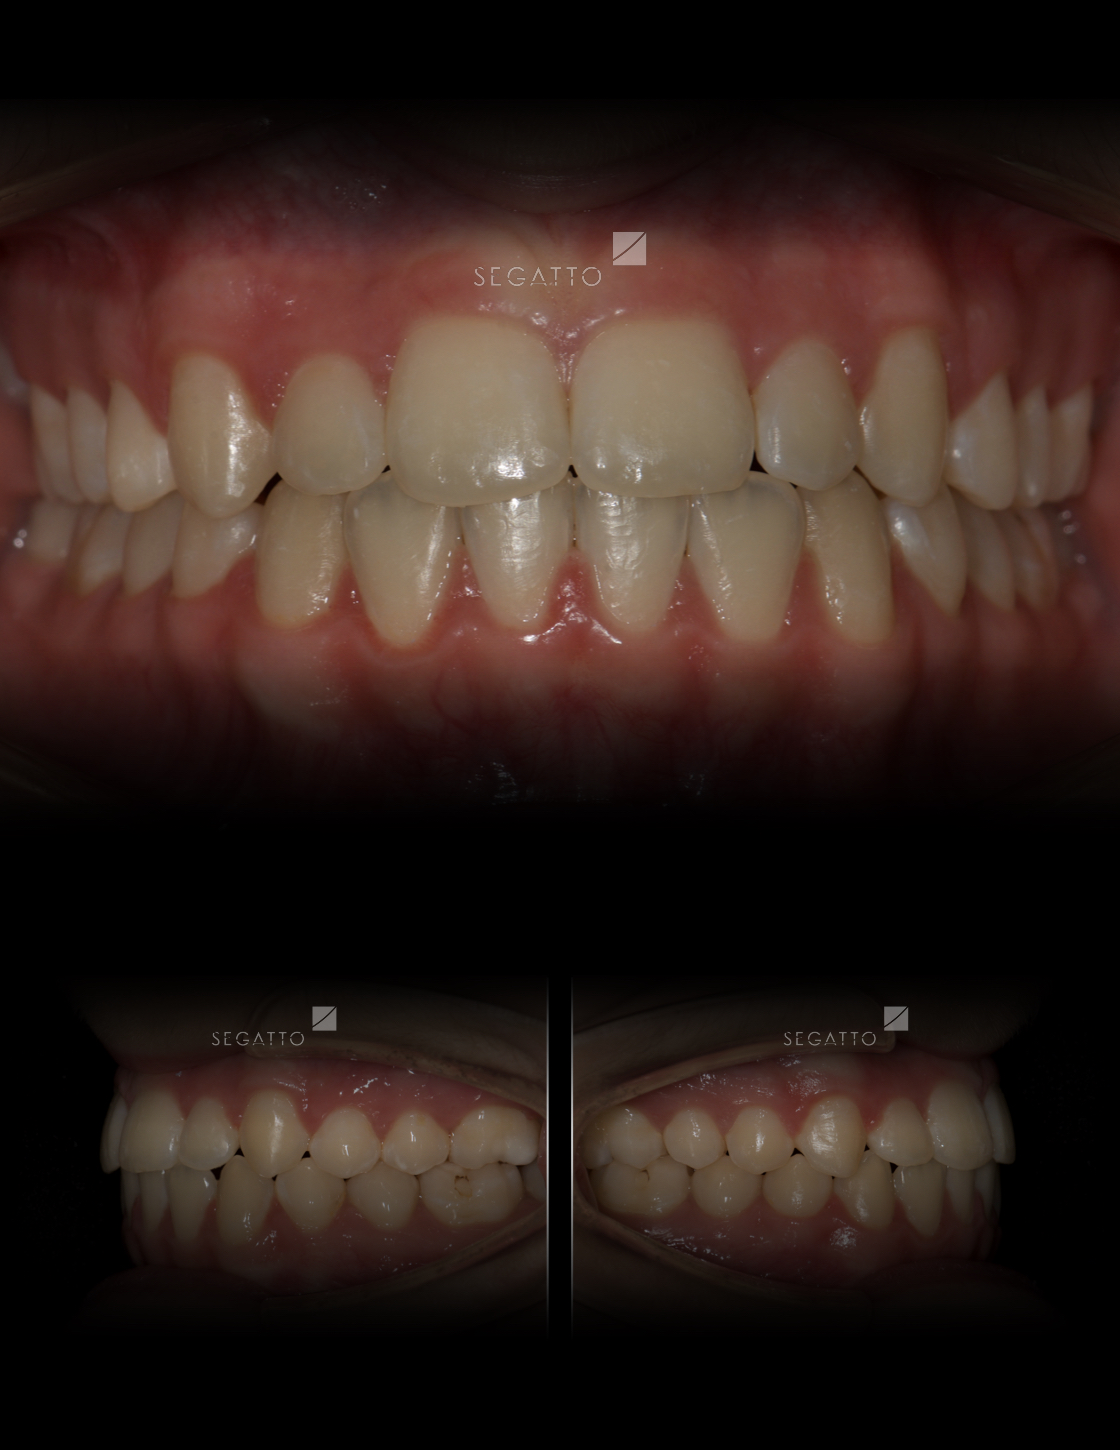

Orthodontics

Cases